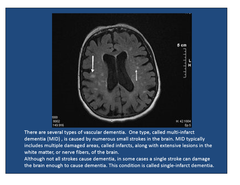

vascular dementia

Front

disease caused by numerous small cerebral vascular accidents symptoms: gait abnormalities, dementia, pseudobulbar signs, will see multiple bilateral, gray matter and white matter infarcts